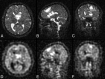

At ultra-high magnetic fields, such as 7T, MR imaging can noninvasively visualize the brain in unprecedented detail and through enhanced contrast mechanisms. The increased SNR and enhanced contrast available at 7T enable higher resolution anatomic and vascular imaging. Greater spectral separation improves detection and characterization of metabolites in spectroscopic imaging. Enhanced blood oxygen level-dependent contrast affords higher resolution functional MR imaging. Ultra-high-field MR imaging also facilitates imaging of nonproton nuclei such as sodium and phosphorus. These improved imaging methods may be applied to detect subtle anatomic, functional, and metabolic abnormalities associated with a wide range of neurologic disorders, including epilepsy, brain tumors, multiple sclerosis, Alzheimer disease, and psychiatric conditions. At 7T, however, physical and hardware limitations cause conventional MR imaging pulse sequences to generate artifacts, requiring specialized pulse sequences and new hardware solutions to maximize the high-field gain in signal and contrast. Practical considerations for ultra-high-field MR imaging include cost, siting, and patient experience.